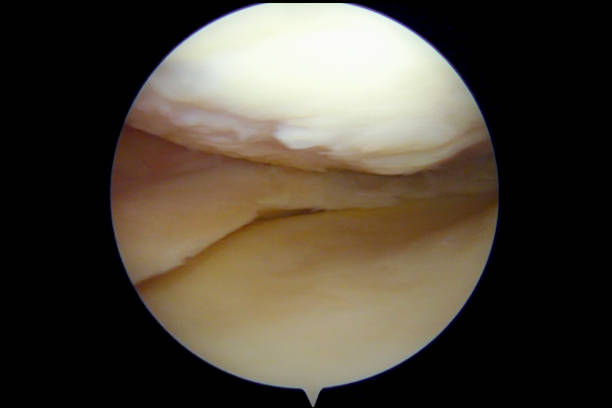

The whole financial side of this is a nightmare too. It’s not about how much the initial visit is, it’s about the whole treatment plan. Think of it like buying a used car. The sticker price is just the beginning. You need to factor in the cost of future repairs (physio sessions), the specialized parts (maybe a brace or a custom insole), and whether the mechanic (the doctor) is going to try to sell you a whole new engine when all you needed was an oil change. You want a doctor who is going to be conservative first, who tries the non-surgical route before pulling out the big scary tools. Statistically, for most common sports injuries, like that pesky ACL tear, while surgery is often necessary, a significant chunk of successful outcomes actually hinge on the quality of the post-op rehab, not just the surgery itself. It’s like 60% operation, 40% sweat equity in the physio gym. People forget that.

There’s a lot of noise online, too. Half the comments on forums are people just sharing horror stories, which is depressing, and the other half are maybe-bots hyping up some random clinic. You have to learn to filter it out. The common thread I always see in the real, positive social media chatter about good sports doctors is a focus on communication and clarity. People don’t mind paying a bit more if they feel truly heard and if the doctor explains the MRI to them not in ‘med-speak’ but in actual human language. “This little tear is like a fray in a rope, and we need to let the body splice it back together,” not “You have a Grade II partial thickness tear of the supraspinatus tendon.” See the difference?